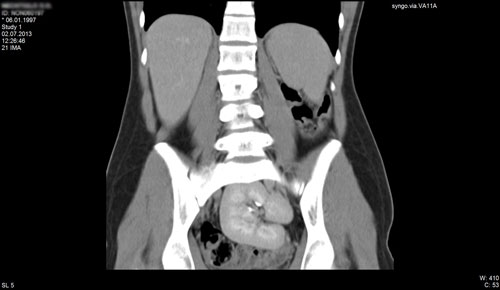

НФП – полная форма резистентности к андрогенам. МРТ органов малого таза (тестикулы в паховых каналах) у фенотипически девочки с кариотипом 46ХУ.